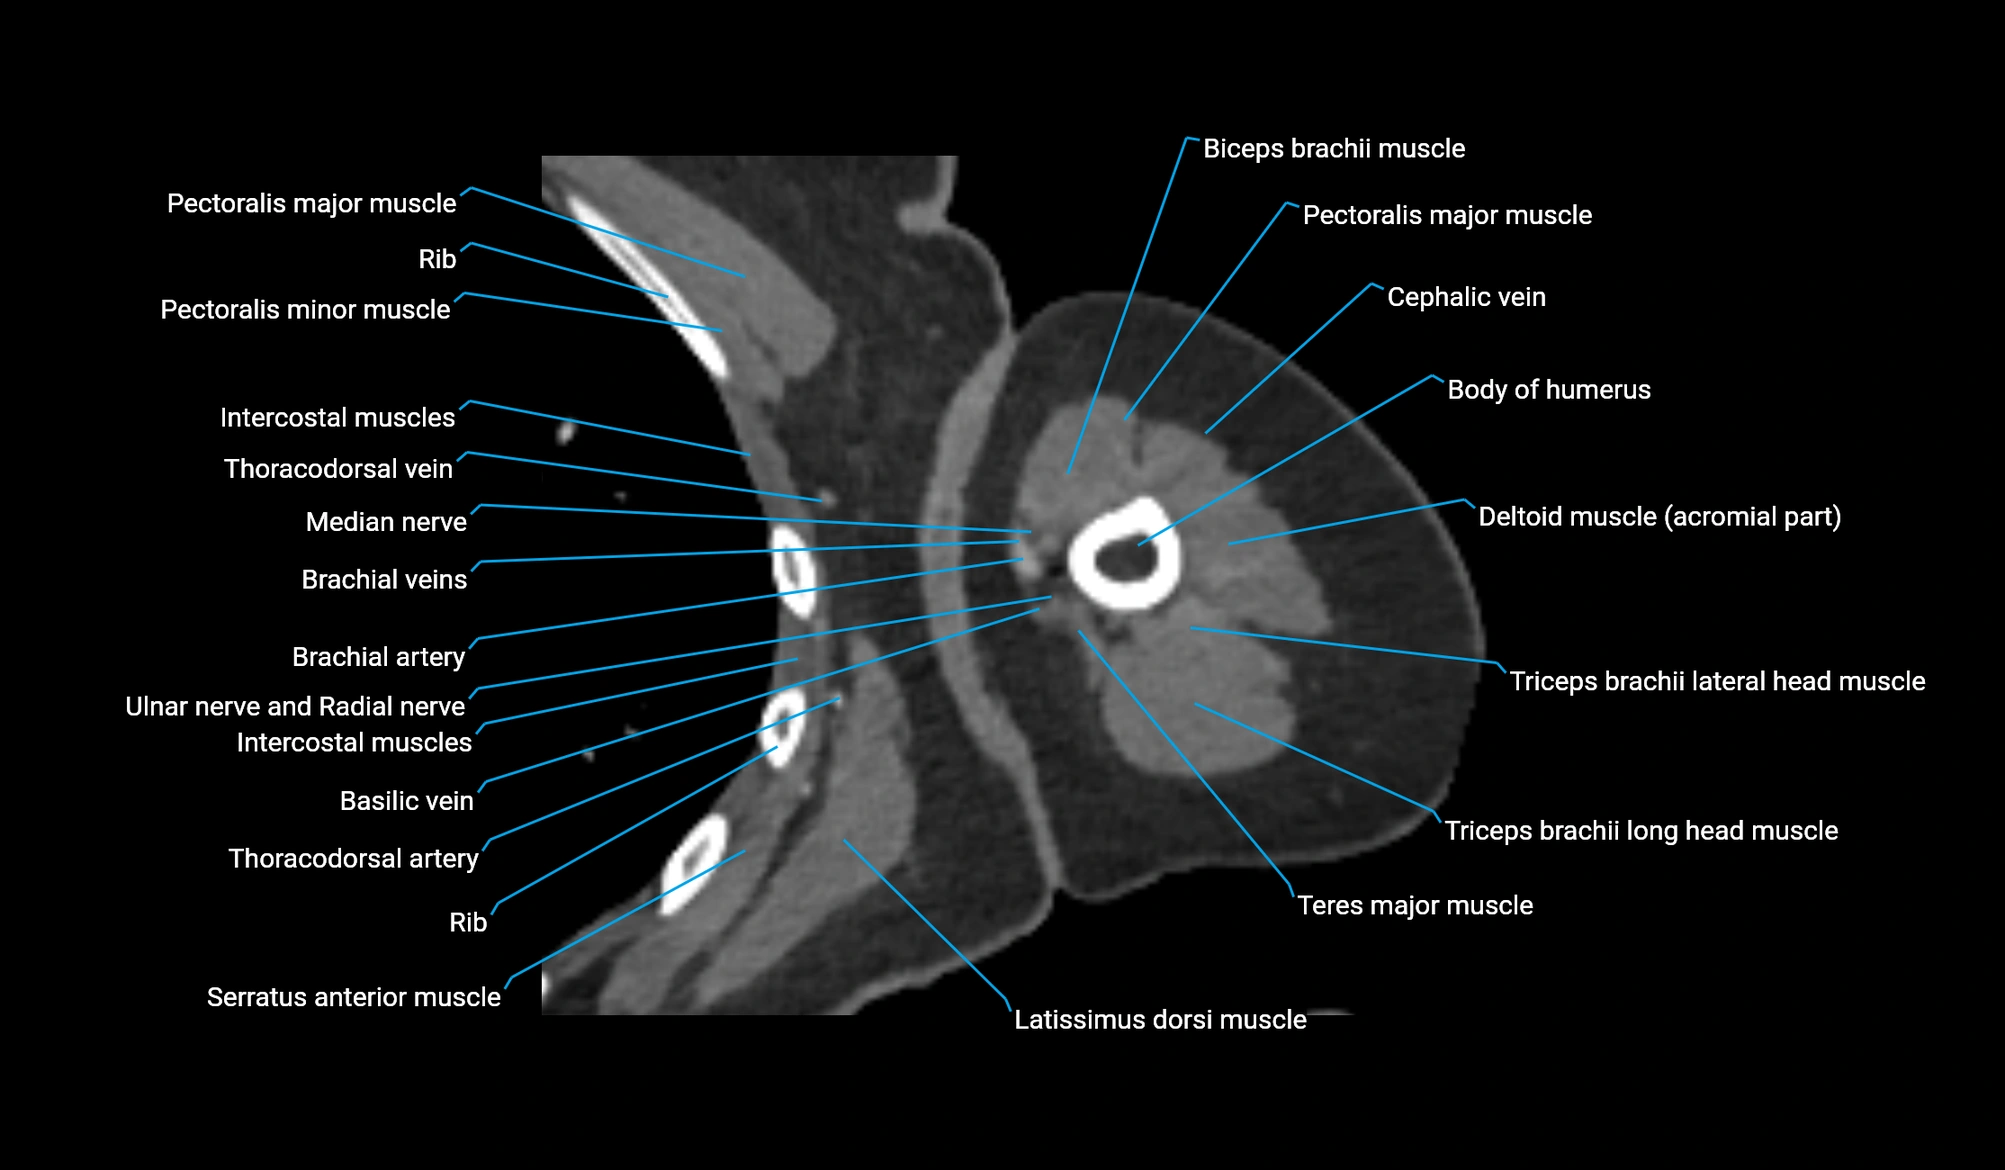

- Body of humerus

- Brachial artery

- Cephalic vein

- Deep brachial artery

- Lateral head of triceps brachii muscle

- Long head of triceps brachii muscle

- Median nerve

- Pectoralis major muscle

- Pectoralis minor muscle

- Radial nerve

- Teres major muscle

- Thoracodorsal artery

- Triceps brachii muscle